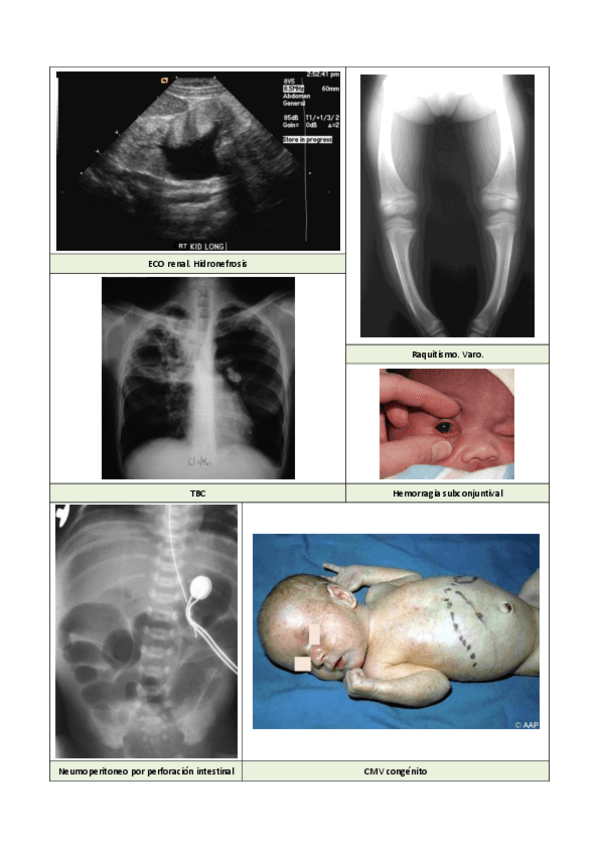

Ecoe Pediatría

He publicado nuevos apuntes de 6º Apuntes Variados: Ecoe Pediatría

Imagenes 2.pdf

imagenes 7 (1).pdf

Imagenes.pdf

Meningitis TBC.pdf